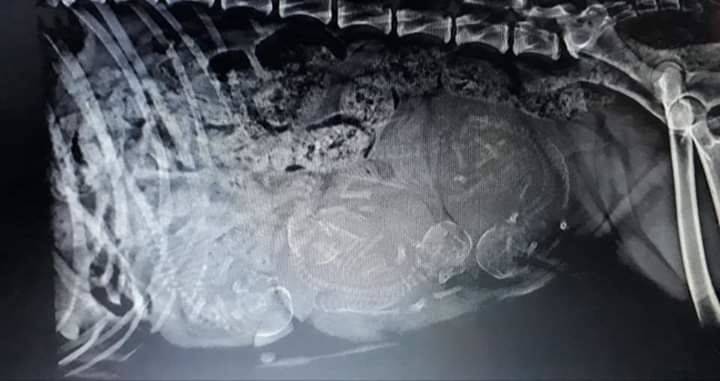

Prima del completo sviluppo è sconsigliato far saltare i cuccioli, e ove possibile meglio evitare le scale. Queste nozioni di prevenzione di base vi verranno sicuramente ribadite nel caso in cui deciderete di intraprendere attività di agility o discdog. Dopo i 12 mesi è consigliabile effettuare le lastre ufficiali ad anche e gomiti. Le due centrali di lettura riconosciute sono: